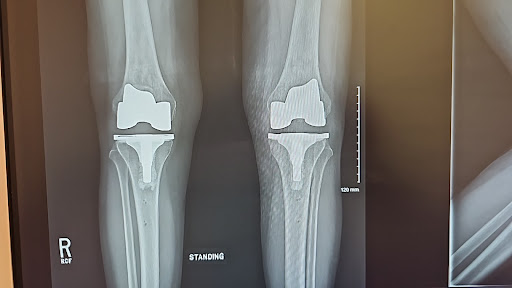

Had robotic total knee reolacemet surgery on my right knee in October and then had my left knee replaced in May. ...read moreread lessBarbara Margolies6/02/2024Excellent Doctor Had robotic total knee reolacemet surgery on my right knee in October and then had my left knee replaced in May. All together I feel 100% better. I am thrilled with the speed of the recovery. My incision looks fantastic, but more importantly, my knee feels amazing. I hardly and anybsututes removes and the skin gkuenqas very comforting. Thank you for doing an amazing job!read moreread lessBarbara Margolies5/21/2024 - I had a painful biceps and arthritis of my shoulder. Dr. Gendy did a right shoulder arthroscopic repair and clean out. My shoulder feels so much better already. I’m 3 months post surgery, done with PT, and back in the gym working out. I’m thrilled with recovery especially at the age of 77.read moreread lessCharlie Leger5/16/2024Outpatient Anterior Total Hip Replacement